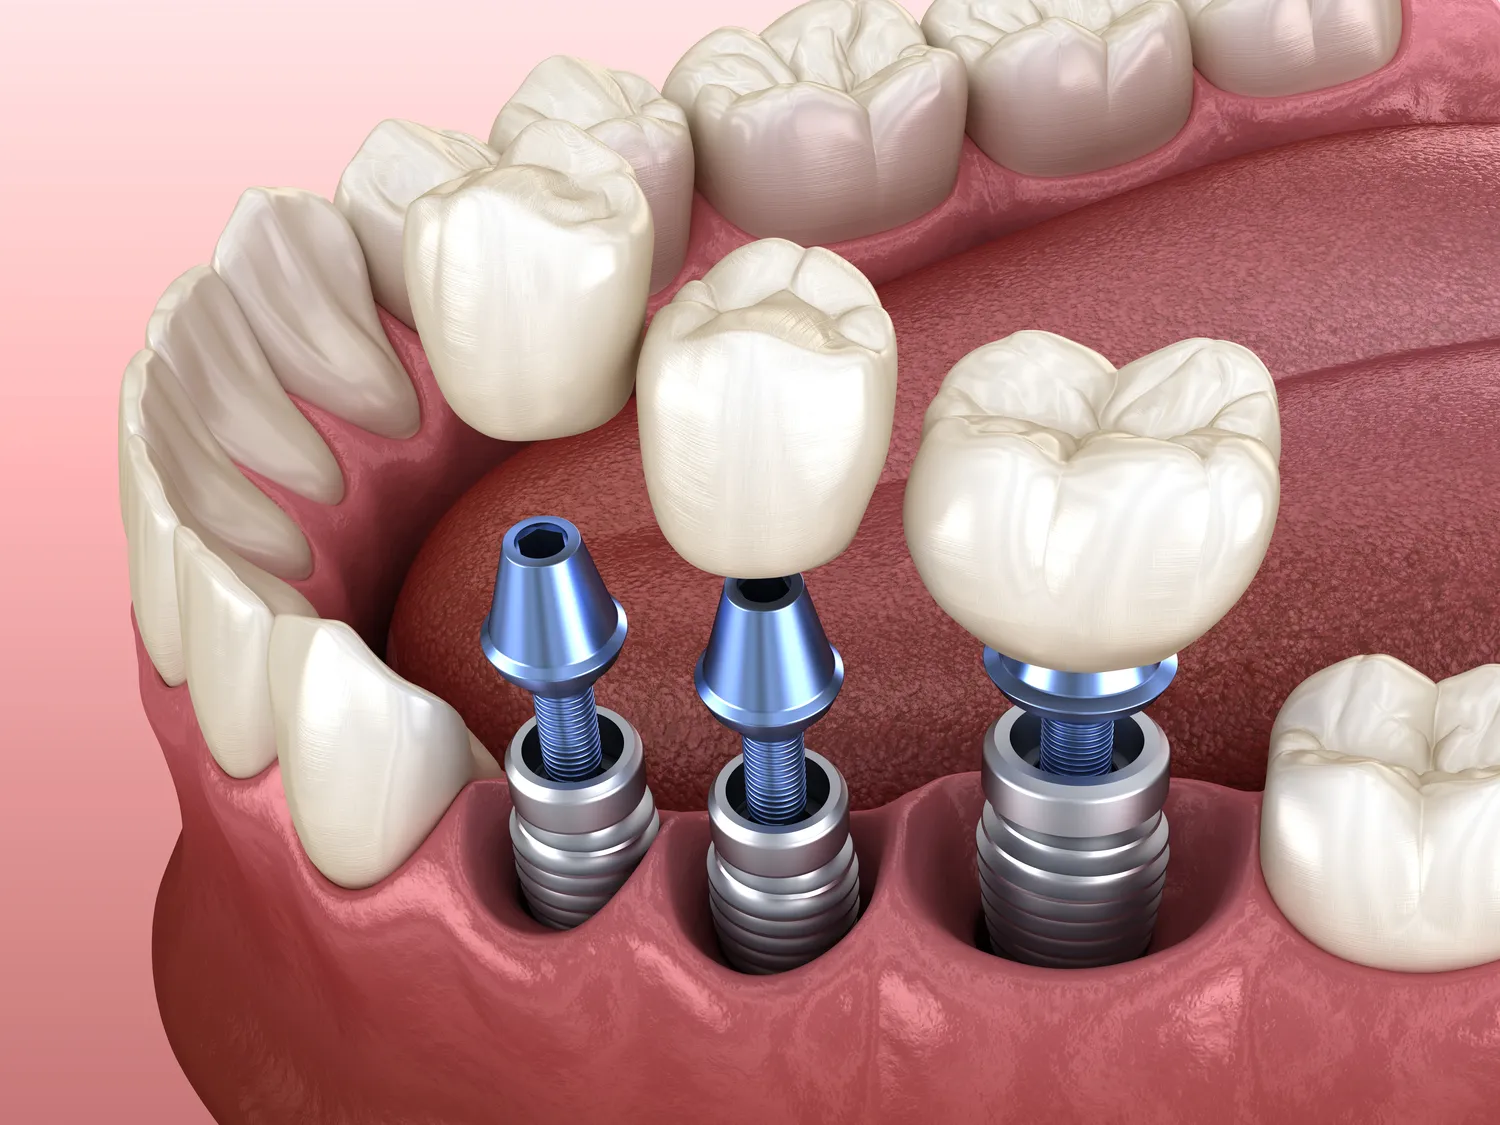

W dziedzinie stomatologii estetycznej i protetyki dostępne są nowoczesne materiały, takie jak wysokiej jakości ceramika czy kompozyty, które pozwalają na stworzenie uzupełnień protetycznych (korony, licówki) idealnie imitujących naturalne zęby. Dostępne są również metody wybielania zębów, które są bezpieczne i skuteczne, a także procedury poprawiające kształt i kolor zębów. Implantologia, czyli metoda odtwarzania utraconych zębów za pomocą implantów, oferuje trwałe i estetyczne rozwiązanie, które przywraca pełną funkcjonalność uzębienia. Nowoczesne techniki chirurgiczne minimalizują okres rekonwalescencji i ryzyko powikłań.

W leczeniu kanałowym (endodoncji) coraz częściej wykorzystuje się mikroskopy stomatologiczne. Pozwalają one dentyście na pracę z niezwykłą precyzją, widząc nawet najdrobniejsze detale kanałów korzeniowych. Dzięki temu możliwe jest dokładne oczyszczenie i wypełnienie kanałów, co znacząco zwiększa szansę na uratowanie zęba i zapobiega nawrotom infekcji. Nowoczesne endometrii (urządzenia do pomiaru długości kanałów) oraz systemy ultradźwiękowe wspomagają pracę endodonty, czyniąc leczenie kanałowe procedurą o wysokiej skuteczności.

Warto również wspomnieć o technikach minimalnie inwazyjnych, które stają się standardem w wielu gabinetach. Dotyczy to zarówno profilaktyki, jak i leczenia. Laser stomatologiczny znajduje zastosowanie w leczeniu stanów zapalnych dziąseł, wybielaniu zębów, a nawet w drobnych zabiegach chirurgicznych. Jego działanie jest precyzyjne i często bezkrwawe, co przyspiesza gojenie. Nawigacja komputerowa w implantologii i chirurgii szczękowo-twarzowej pozwala na precyzyjne umieszczenie implantów czy przeprowadzenie skomplikowanych zabiegów z minimalnym ryzykiem. Wybierając gabinet stomatologiczny, warto zwrócić uwagę na to, czy stosuje on nowoczesne technologie, które mogą znacząco poprawić jakość i komfort leczenia.